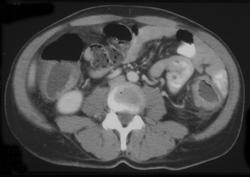

问题 女,40岁,腹痛、腹泻、脓血便、里急后重,结合图像,选择最可能诊断 ( )

选项 A、慢性溃疡性肠炎 B、结肠淋巴瘤 C、结肠克罗恩病 D、结肠结核 E、假膜性肠炎

答案 A